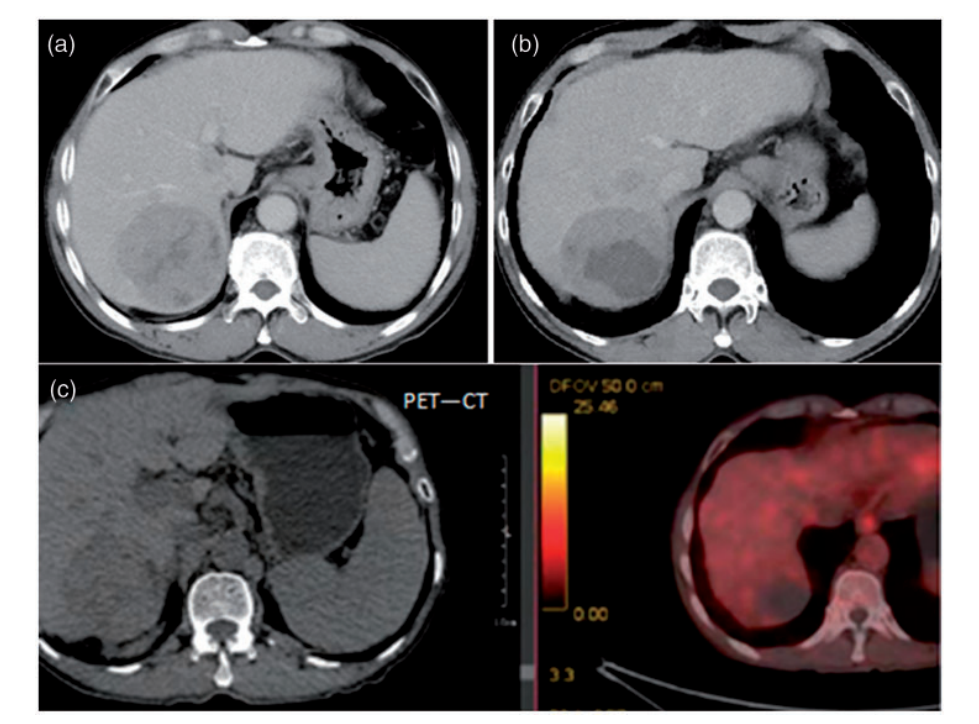

CT扫描和磁共振成像(MRI)显示在右侧前叶、左侧和尾状叶弥漫性动脉高血管/门静脉洗脱团块,侵犯主干、右侧前叶、左侧门静脉、左肝静脉和下腔静脉。肝硬化,门脉高压,脾肿大,腹膜后淋巴结也被观察到。

患者接受肝细胞癌RFA和瘤内注射rhAd5(1.0*10^12病毒颗粒,1次),此外,术后每3周静脉给予帕博利珠单抗(每次200 mg) 1次。恩替卡韦常规用于抑制HBV复制。治疗6周后复查肿瘤标志物,AFP和PIVKA-II分别降至10.090 ng/mL和25.00 mAU/mL。治疗5个月后复查增强CT,肿瘤及肿瘤血栓较治疗前明显缩小。再次MRI增强检查发现肝左叶及尾状叶斑片状异常信号影明显变小,肿瘤血栓消失或缩小。

他接受相同的治疗方案,并在6个月后根据PET-CT扫描达到CR。然而,该患者并没有进行手术来确认肿瘤细胞是否消失。目前,该患者已存活24个月以上,无任何症状。监测了两例患者的不良反应,没有证据表明联合治疗的副作用增加。